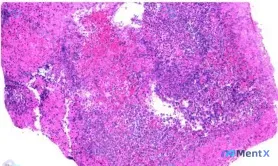

初始病理只提了回盲部黏膜坏死、出血、炎症;

进一步影像分析看到了组织架构完全破坏、大片凝固性坏死、弥漫性“异型细胞”,直接指向了高级别恶性肿瘤伴坏死;

但还有另一种声音——这个位置、这个形态,会不会是感染/缺血的形态学假象?比如结核的干酪样坏死、阿米巴的溃疡坏死、甚至缺血性肠病的坏死,会不会把反应性细胞误读成“肿瘤细胞”?